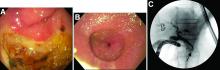

This patient has a known history of prepyloric peptic ulcer disease and related gastric outlet obstruction requiring two previous dilations. Upon endoscopic examination, we observed high-grade obstruction at the pylorus similar to previous examinations. During the initial positioning of the balloon for dilation, we inadvertently cannulated the fistula located in the pyloric channel using the guidewire (arrow in Figure D) and were able to characterize its anatomy upon contrast administration (Figure C). However, after repositioning the guidewire into the duodenal lumen beyond pyloric stricture, the balloon was inflated to a maximal diameter of 15 mm under fluoroscopic guidance. Discounting other common causes, our patient presented with an infrequent occurrence of choledocopyloric fistula secondary to peptic ulcer disease.